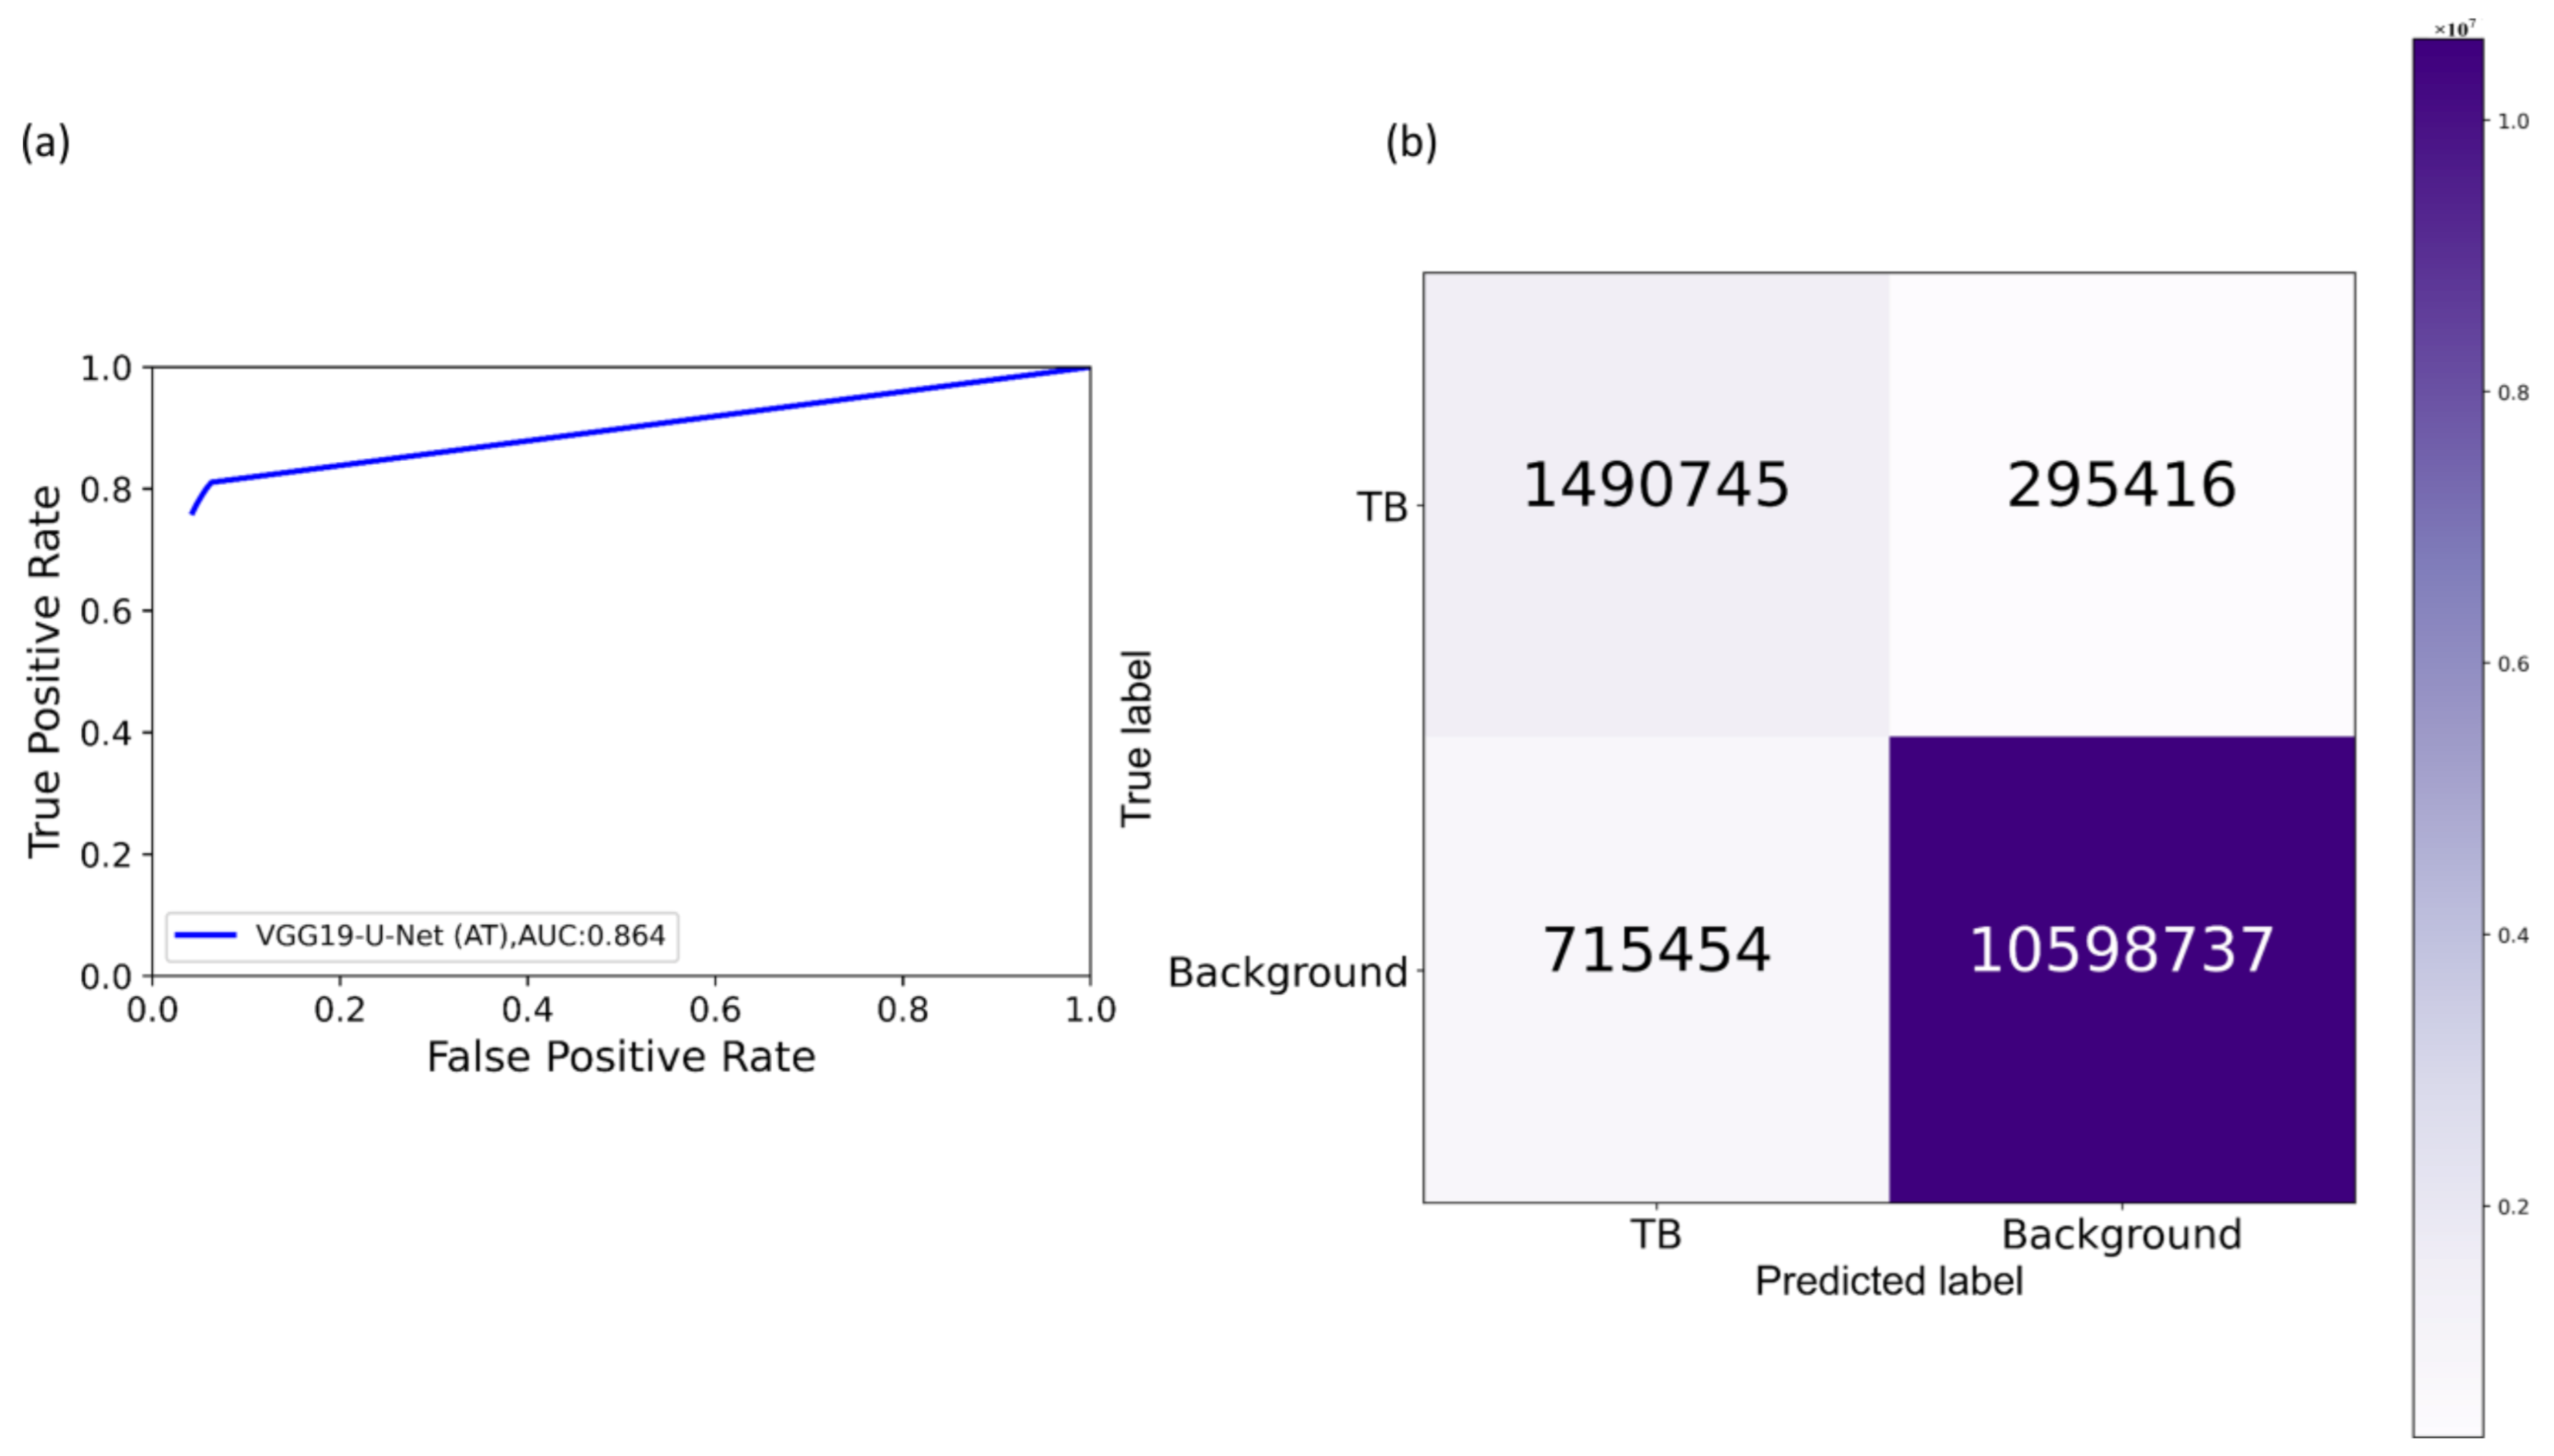

Section 2.4 to segment the lungs in this collection. Following lung segmentation, we rescaled the disease bounding box coordinates and converted them into binary masks. Recall that since we are using bounding boxes for training, a fraction of the pixels within these are false-positive (FP) training labels, which adversely impact our outcome. These masks and their associated CXRs are used to train and test the models. We used a fixed seed value to allocate 10% of the training data toward validation. Variability is introduced into the training process by augmenting the training data through affine transformations, including horizontal flipping, height and width shifting, and rotations. Callbacks are used to store model checkpoints, and the best performing model is used to segment TB-consistent ROI.

We further evaluated the performance of the U-Net models with cross-institutional test sets. The Shenzhen TB CXR-Subset-2 (n = 68) and the Montgomery TB CXR (n = 58) collections are individually used as test sets toward this evaluation. Such cross-institutional testing would demonstrate the generalization ability of the models and their suitability for real-time deployment because the test set is diverse and unseen during the training process.

2.8. Selecting Appropriate Loss Function and Other Evaluation Metrics

U-Net models, though having an excellent potential toward accurate medical image segmentation, often suffer from data imbalance. These issues are particularly prominent in applications that involve lung/TB-consistent ROI segmentation, where the number of lung/TB-consistent ROI pixels is markedly lower compared to the total image pixels. Such imbalanced training may lead to learning bias and may adversely impact segmentation performance. To alleviate issues due to these data imbalances, a generalized loss metric based on the Tversky index has been proposed [

Here a and b denote the set of predicted and GT binary labels, respectively, a0k is the probability of the pixel k to belong to the lung/TB-consistent ROI, a1k is the probability of the pixel k to belong to the background, b0k takes the value of 1 for a lung/TB-consistent ROI pixel and 0 for the background and vice versa for b1k. Through empirical evaluations, we observed that the values for the hyperparameters α = 0.3 and β = 0.7 demonstrated a good balance between precision and sensitivity and that higher values for β resulted in improved performance and generalization while using imbalanced data and helped to boost sensitivity. Accordingly, we used these hyperparameter values in the current study. We used callbacks to store model checkpoints after the completion of an epoch. The best of the stored checkpoints is used as the final model for the subsequent analysis.

We measured segmentation performance in terms of the following metrics: (i) confusion matrix; (ii) Jaccard index, otherwise known as the intersection of union (

Selecting the appropriate loss function: segmentation models often suffer from class imbalance issues, particularly in medical image segmentation tasks. This is due to the highly localized ROI, spanning for a very small percentage of the total number of image pixels. The issues with using the conventional BCE loss for such class imbalanced segmentation tasks are as follows: (i) the BCE loss weighs all image pixels equally; (ii) the model demonstrates low BCE loss and hence higher segmentation accuracy even if it misses all ROI pixels that spans a small portion of the total image. In this study, we used a customized loss based on Tversky Index, an asymmetric similarity measure that generalizes IOU and Dice metrics. The use of a customized Tversky index-based loss function with empirically determined hyperparameter values for the problem under study helped to improve segmentation performance by providing a finer level of segmentation control compared to using a conventional BCE-based loss. Computing a single precision and recall score at a specific IOU threshold does not sufficiently describe the models’ behavior. In this study, we used AP@[0.5:0.95] to effectively integrate the AUPRC by averaging the precision score at multiple IOU thresholds ranging from 0.5 to 0.95 (in 0.05 increments). Such a measure would help to better demonstrate models’ generalization ability and stability toward the segmentation task.